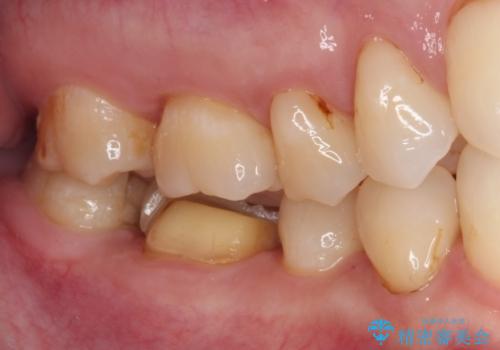

- セラミッククラウンが度々欠けてしまうとのことで来院された患者様です。

セラミッククラウンを装着するには、削る量がやや少ない印象であったので、クラウン破折リスクを回避するために削る量を少し増やすこととしました。

また、咬合力が強いため、強化セラミックのみで製作するフルジルコニアクラウンにて補綴治療することとしました。

フルジルコニアクラウンは、強度が高い反面、審美性に欠けるため、前歯部に装着することはお勧めできません。